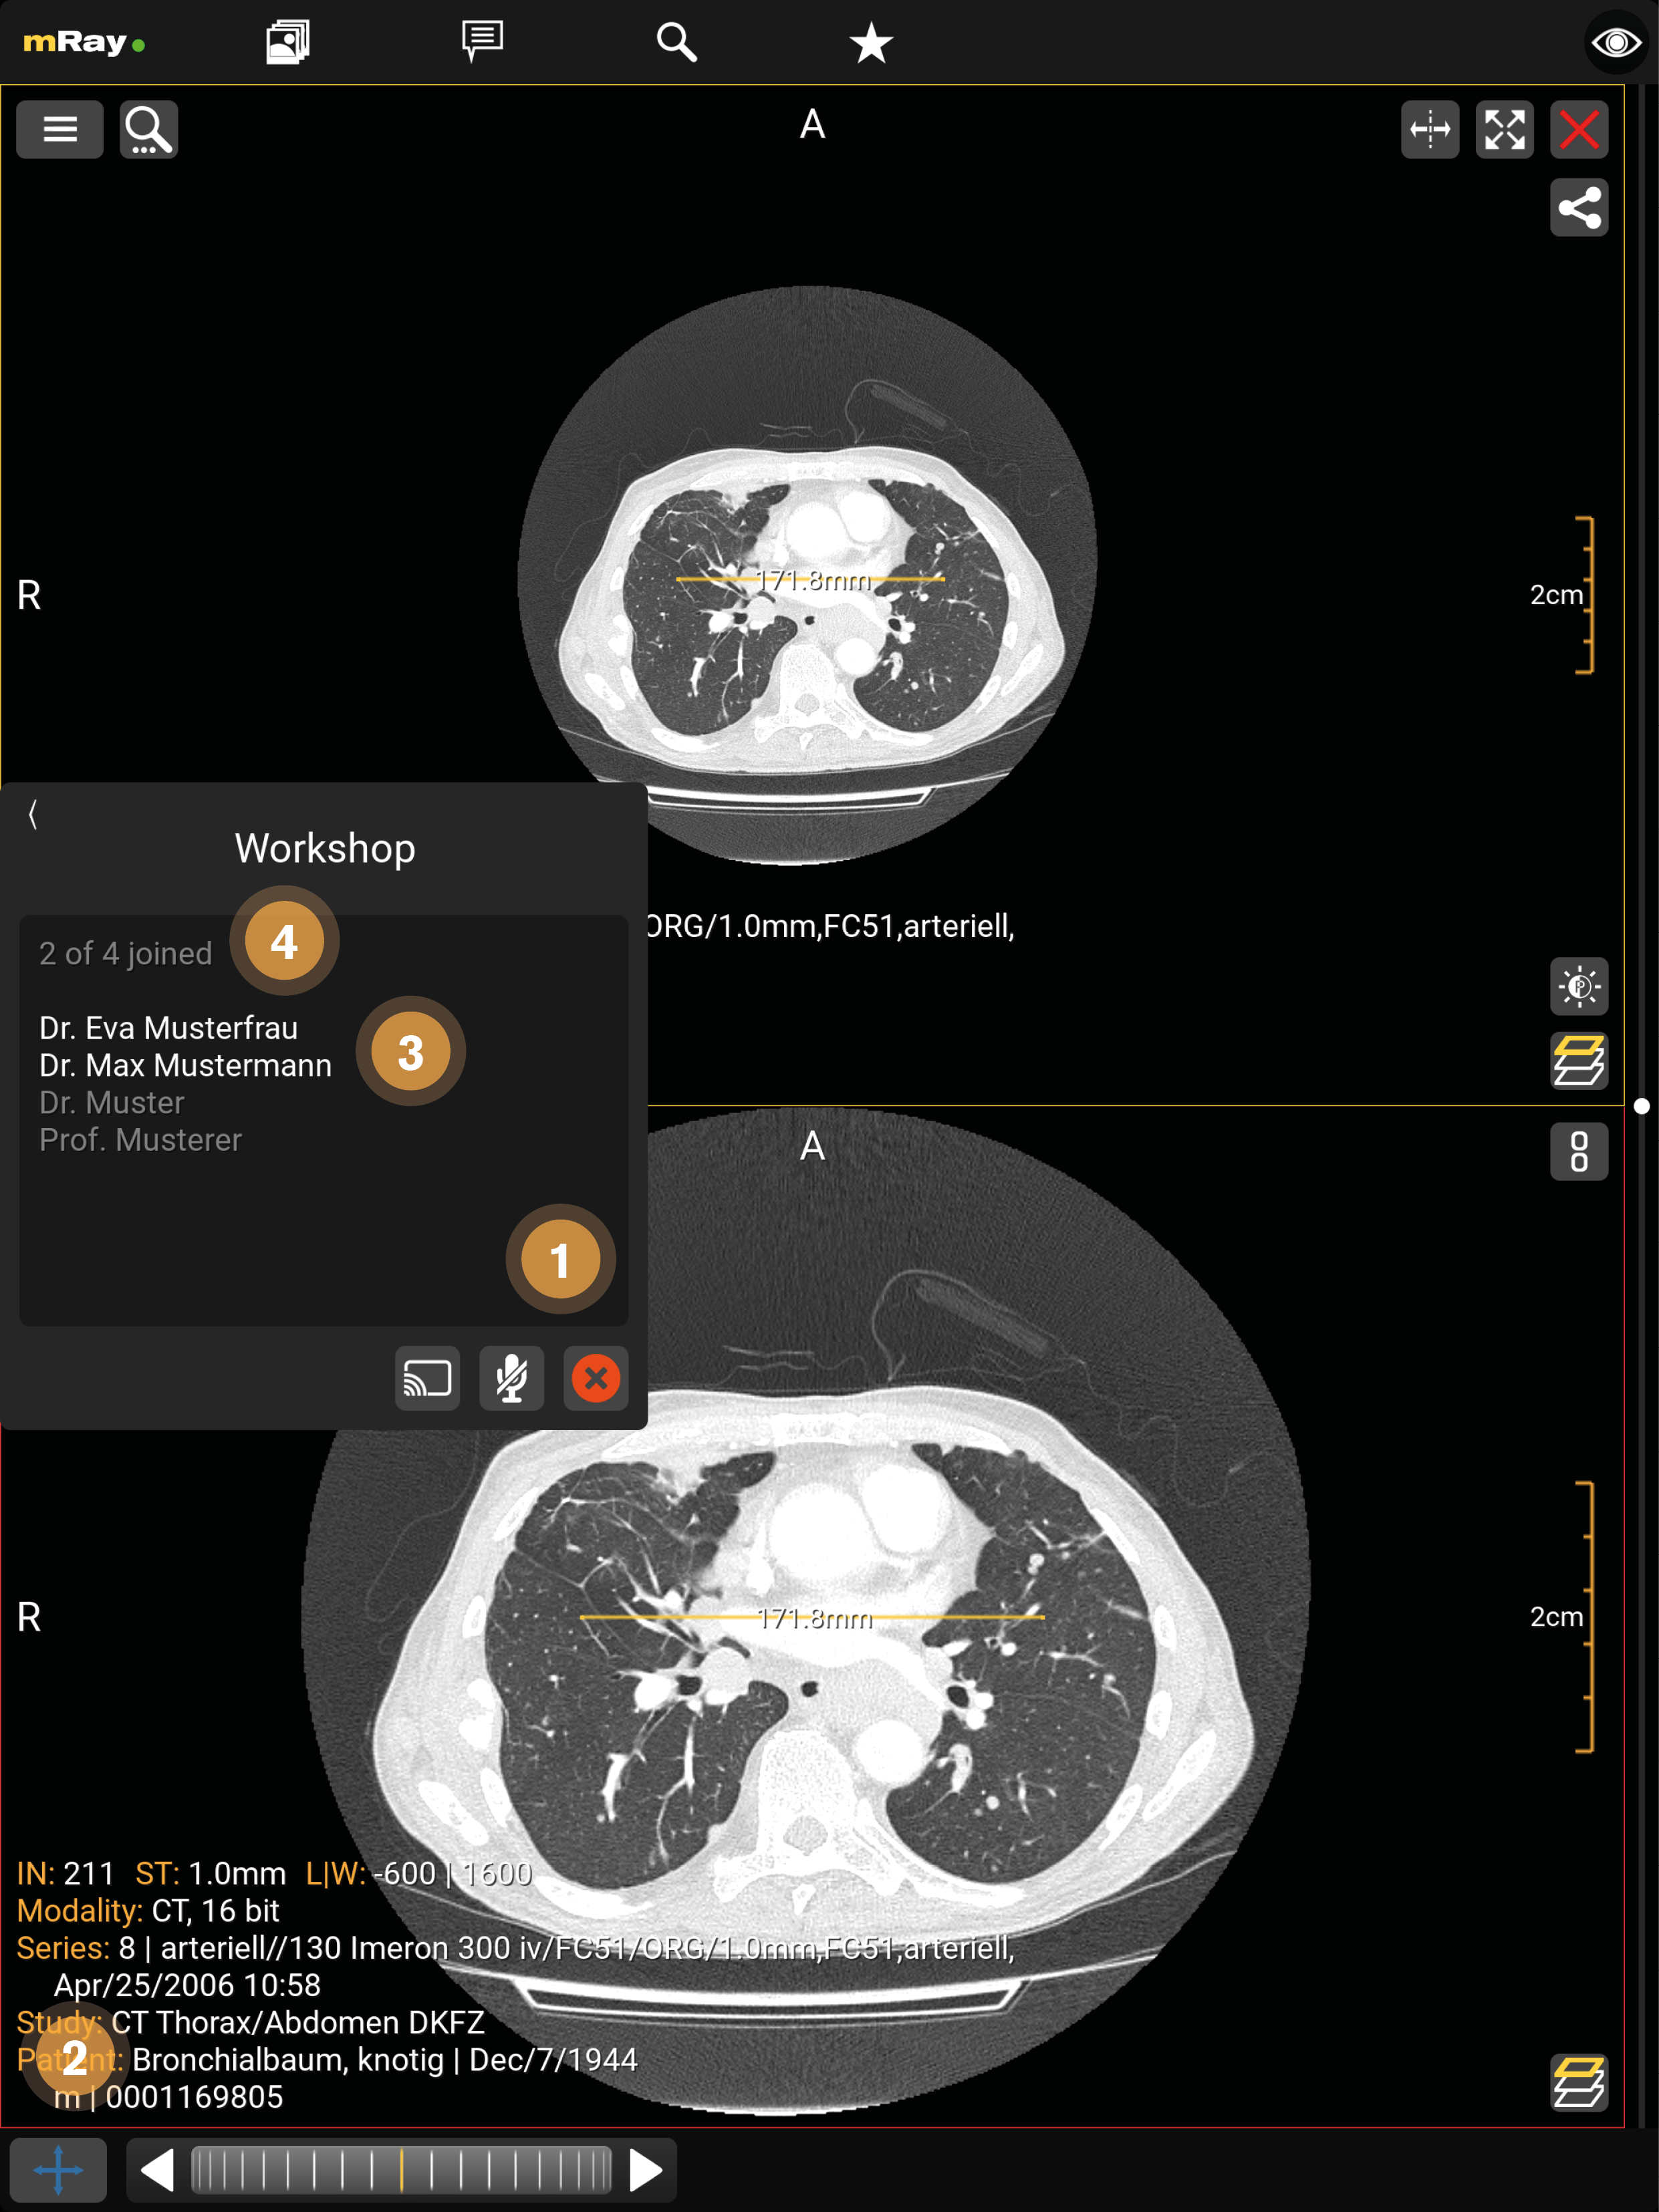

14. Screensharing

Das Screensharing ermöglicht es, Ihren Bildschirm mit anderen zu teilen. Nach der Betätigung des Buttons (siehe Chat) startet das Screensharing und es öffnet sich das bereits von Ihnen geöffnete Bild (siehe Chat) oder Sie werden an die Inbox weitergeleitet, wenn noch kein Bild geöffnet wurde. Das Screensharing kann mit einer oder mehreren Personen (siehe Screensharing in Gruppen), in Form einer Gruppe, gestartet werden.

In einem Chat ist derjenige Administrator, der das Screensharing startet. In einer Gruppe wird der Administrator zuvor festgelegt (siehe Screensharing in Gruppen).

Die Ansicht stellt folgende Funktionen zur Verfügung:

-

Derjenige der das Screensharing gestartet hat wird weiß unterstrichen, die aktiven Teilnehmer werden weiß und die inaktiven Teilnehmer der Gruppe grau dargestellt.

-

Mit dem "Mikrofon"-Button kann ein Teilnehmer die Sprachfunktion aktivieren und beenden (durchgestrichen). Der sprechende Teilnehmer wird gelb dargestellt.

-

Durch den X-Button kann das Screensharing verlassen werden.

-

Nur der Administrator kann während des Screensharings Werkzeuge anwenden.

-

Hier kann das Fenster minimiert werden.

Die Ansicht stellt folgende Funktionen zur Verfügung:

-

Durch den "grüner Haken"-Button kann der Teilnehmer dem Screensharing beitreten.

-

Der Administrator wird weiß unterstrichen, die aktiven Teilnehmer werden weiß und die inaktiven Teilnehmer der Gruppe grau dargestellt.

14.1. Screensharing in Gruppen

In einer Gruppe kann das Screensharing nur von einem zuvor bestimmten Administrator gestartet werden. Für die anderen Teilnehmer der Gruppe startet das Screensharing automatisch. In einer Gruppe kann nur der Administrator der Gruppe die Sprachfunktion verwenden.

Die Ansicht stellt folgende Funktionen zur Verfügung:

-

Durch den X-Button wird das Screensharing für alle Beteiligten beendet.

-

Nur der Administrator kann während des Screensharings Werkzeuge anwenden.